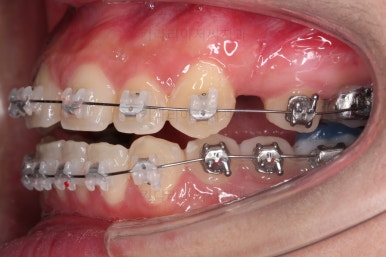

우선 장치를 부착했습니다.

이번에 선택한 장치는 엠파워 클리어라고 하는 자가결찰 세라믹 장치인데요.

흔히 아시는 클리피씨 장치와 같은 분류의 장치입니다. 클리피는 일본, 엠파워는 미국 제조사라는 차이가 있지만 큰 틀에서는 세라믹 바디에 금속 클립이 달린 거의 동일한 장치라고 보시면 됩니다.

장치 부착 직후의 모습인데요.

장치가 보이는 느낌이나 옆라인의 변화 양상은 참고해 주세요.

부산치아교정 이번 치료의 핵심인데요.

결손 부위에 미니스크류를 이용해서 뒤쪽 어금니들을 결손 부위로 앞으로 앞으로 계속 당겨줍니다.